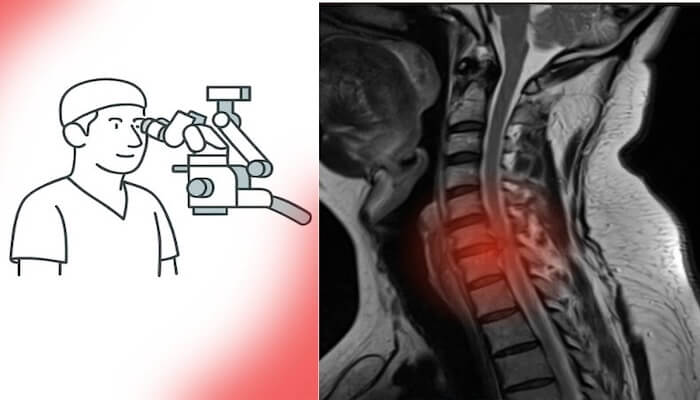

veya linki kopyala

Son yıllarda beyin ve omurga cerrahisinde hasta profili belirgin biçimde değişti. Artık ameliyat masasında sadece ileri yaşlı hastalar değil, genç erişkinler de yer alıyor. Özellikle bel fıtığı ameliyatı, boyun fıtığı ameliyatı ve hatta beyin tümörü ameliyatı geçiren hastaların yaş ortalaması giderek düşüyor. Peki bu değişimin sebepleri neler?